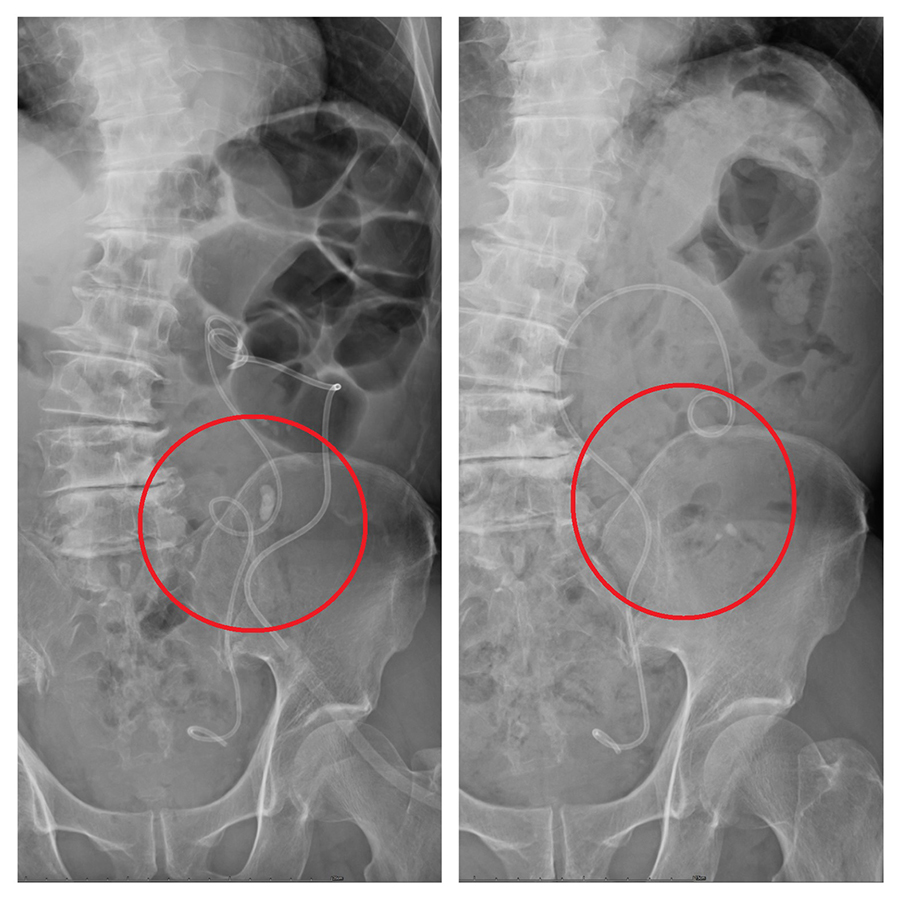

衛生福利部豐原醫院泌尿科主任林德祺表示,原本計畫採用傳統硬式輸尿管鏡取石,但由於患者輸尿管嚴重彎曲,如同雲霄飛車軌道,鏡體根本無法進入,醫療團隊迅速啟用最新一代「7.5Fr軟式輸尿管鏡」,細如筆身,靈巧自如,能靈活穿梭於曲折如迷宮的輸尿管中,隨著鏡頭抵達結石處,高能雷射瞬間擊碎石塊,搭配可彎可吸導管同步吸出碎屑,手術過程一氣呵成,最終成功解除阻塞,讓腎臟壓力釋放、尿路再現通暢。